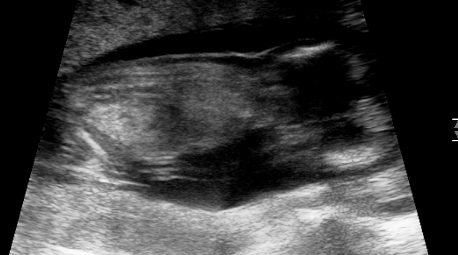

Guesses anyone? Was told boy at 12w2dAttachment 18706Attachment 18707Attachment 18708

Poss girl but not sure that's the nub?!?

I don't see a nub. How many weeks are you?

12w2d

Too early for a potty shot, and I don't see a nub. But I don't see anything obvious in the potty shot, so slight girl lean.

No nub, can't go by potty shot.